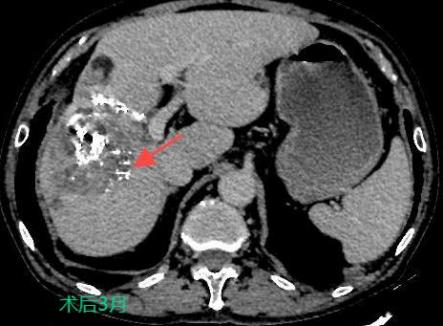

TACE/HAIC:經(jīng)肝動(dòng)脈灌注化療栓塞(TACE)、肝動(dòng)脈內(nèi)灌注化療藥物(HAIC)是在不開(kāi)刀暴露腫瘤病灶的情況下,在皮膚上做直徑幾毫米的切口,在影像設(shè)備的引導(dǎo)下,導(dǎo)絲和導(dǎo)管插入肝臟腫瘤血管,注入栓塞劑和化療藥物使肝臟腫瘤內(nèi)化療藥物濃度提高,并減少全身的藥物總濃度,達(dá)到提高化療效果并減少毒副作用的目的。對(duì)于無(wú)法手術(shù)切除的巨塊型肝癌、肝內(nèi)多發(fā)肝癌病灶、肝癌結(jié)節(jié)破裂出血有良好的治療效果。

bd76aa52bb6546a69be60729c8730795.Jpeg

7c270a27028043a8ba4cb33fa1c0ed79.Jpeg

097218efe36240c99faa29fefe0fd54e.Jpeg

癌的介入治療